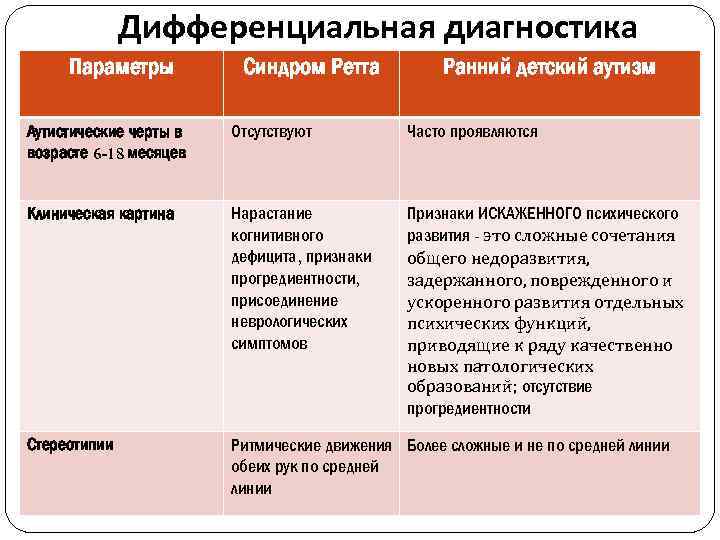

Дифференциальная диагностика Параметры Синдром Ретта Ранний детский аутизм Аутистические черты в возрасте 6 -18 месяцев Отсутствуют Часто проявляются Клиническая картина Нарастание когнитивного дефицита, признаки прогредиентности, присоединение неврологических симптомов Признаки ИСКАЖЕННОГО психического развития - это сложные сочетания общего недоразвития, задержанного, поврежденного и ускоренного развития отдельных психических функций, приводящие к ряду качественно новых патологических образований; отсутствие прогредиентности Стереотипии Ритмические движения Более сложные и не по средней линии обеих рук по средней линии

Стереотипные манипуляции с предметами Отсутствуют Типичны Моторика туловища и походка Прогрессирующие атаксия и апраксия Манерность, иногда грациозность позы и походки Судорожные припадки Значительно большие частота и полиморфизм Значительно меньше частота и полиморфизм Расстройства дыхания, бруксизм, замедление роста головы и конечностей Типичны Отсутствуют Продолжительность аутистических черт 1 -2 стадии На протяжении всей жизни Инструментальное обследование Не информативно